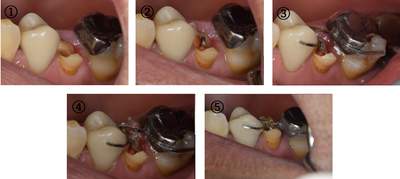

カリエス除去し、MTMを行ったのち、補綴を行う

全体的に10年以上前の治療痕で、銀歯の下でカリエスになっています。今回は右上5に限っての方針を記載する。 |

カリエスを取り除くと、遠心の歯質が歯肉縁下になりました。

MTM開始直後と、終了後です。フックの位置が変わっているのがわかると思いますが、それが歯が動いた証拠となります。

MTM中。頬側には審美面の回復のために仮歯がついています。

歯からはフック、隣り合った歯にはワイヤーが渡してあります。そこにゴムをひっかけて歯を挺出させます。